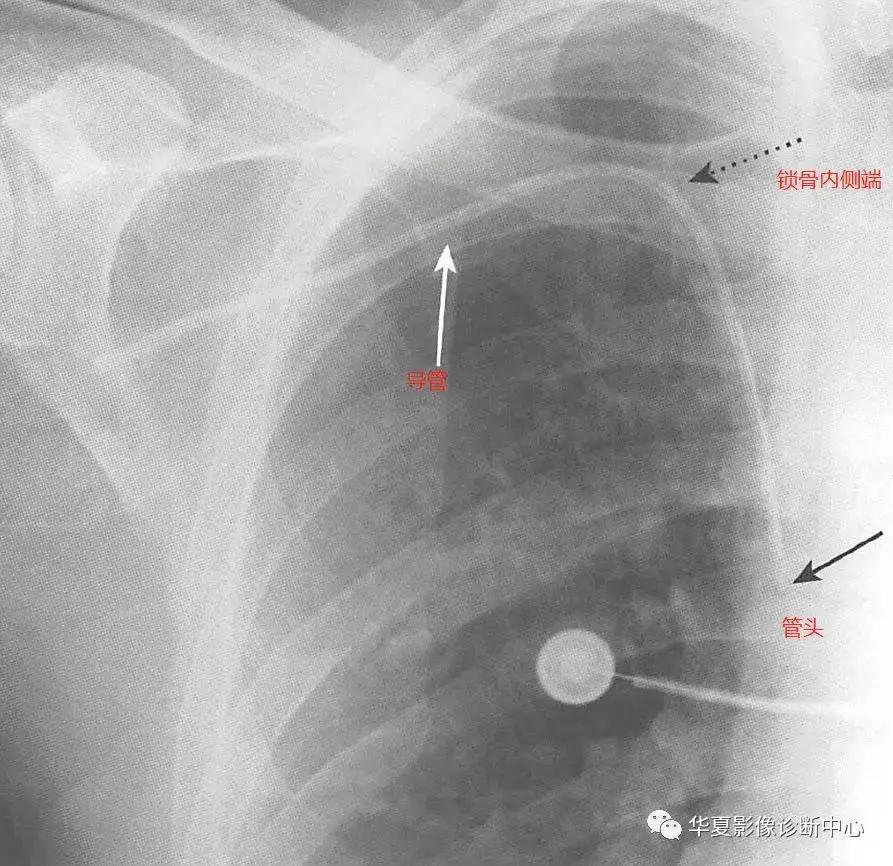

三、中心静脉导管(CVC)

中心静脉导管为无标志条的均匀不透光细导管(直径约3mm),通常由锁骨下静脉或颈内静脉插入,颈内静脉汇入锁骨下静脉形成头臂静脉,再汇入上腔静脉,锁骨下静脉和头臂静脉交汇处通常位于锁骨内侧端后方。CVC下行前应到达锁骨内侧端,管头应位于第一肋前端内侧,导管应沿胸椎右缘向下走行,管头应位于上腔静脉内,导管的弯曲应该是平滑的,而不是锐利弯折;最常见的位置异常发生在右心房或颈内静脉内,插入后,不论成功与否,都要检查是否发生气胸。